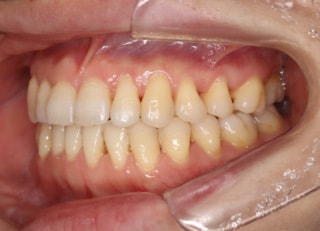

治療前

治療後(2年4ヶ月後)